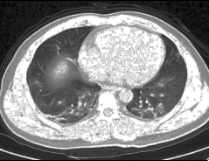

3. Dataset

We worked on lung images from the different datasets for enhancement. We selected lung images from the dataset which is available on Github [22]. The COVID-19 CT database contains 349 CT images which have clinical findings of COVID-19 extracted from 216 patients. We also selected some images from the IQ-OTH/NCCD - lung cancer database [23]. This database includes 1190 images that show CT scan slices of 110 patients. We selected lung images from the dataset which is available on Kaggle [24] also.

The Kaggle dataset is collection of 2-dimensional and 3-dimensional lung images with respective segmented masks. We used only 2-dimensional lung images from the dataset for enhancement and segmentation.